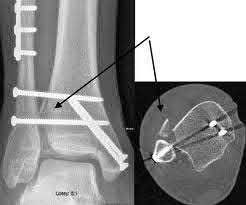

A 25-year-old male sustains an ankle fracture dislocation and undergoes open reduction and internal fixation. He returns to clinic five months following surgery complaining of continued ankle pain and instability with weight bearing. His immediate post-operative AP radiograph is seen in Figure A. Which of the following could have prevented this patient from developing persistent pain?

The patient presents with continued ankle pain and instability following open reduction and internal fixation. The radiograph in figure A demonstrates inadequate restoration of fibular length, likely leading to continued tibiotalar instability.

Illustration A demonstrates fibular malreduction with dislocation of the fibula anterior to the tibial incisura. Illustration B shows a comminuted fibula fracture along with a measurement of length from an intact fibula. The arc from the lateral process of the talus to the peroneal groove of the distal fibula is known as the "dime" sign and should remain unbroken if fibular length has been restored. Illustration C demonstrates the use of a push-pull screw and lamina spreader to regain length intraoperatively for a comminuted fibula fracture.